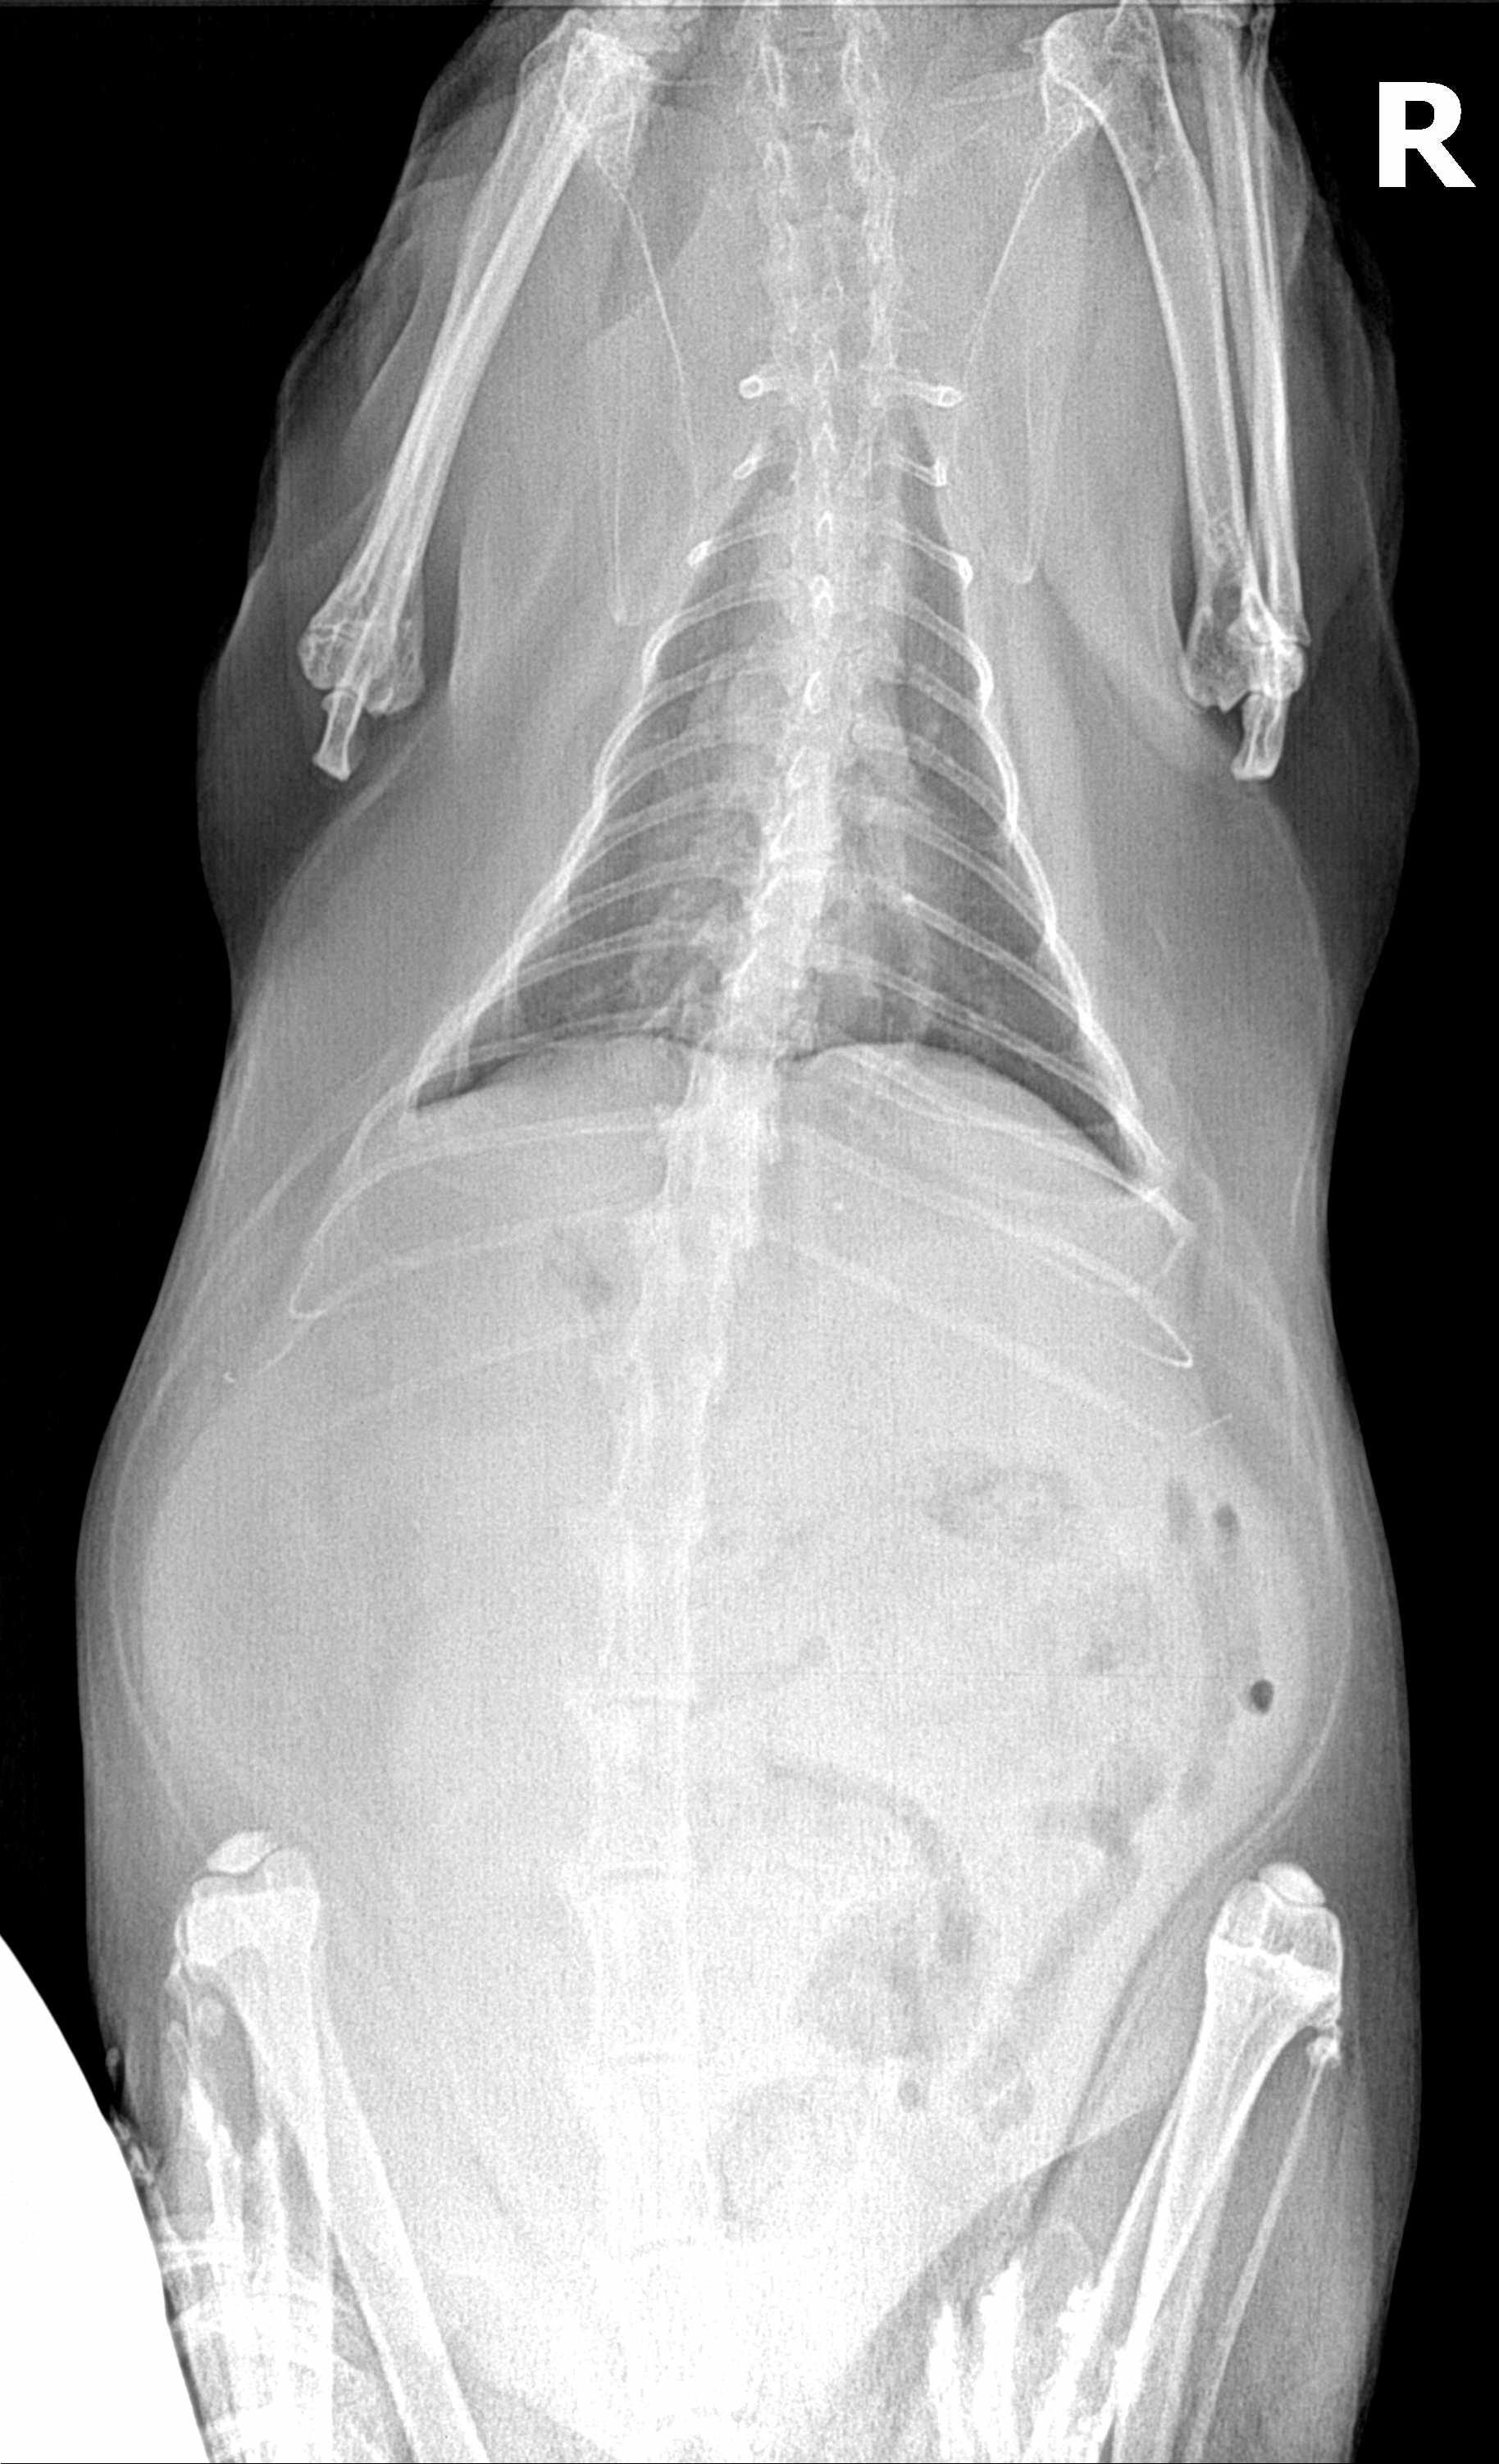

Took my cat to our local vet on Thursday for a bloated abdomen. No other symptoms. Vet found fluid in the abdomen on the xray and increased white blood cell count and said we need an ultrasound to get a real diagnosis. To get one in a timely fashion, we'll need to go to the ER. If the cat is eating, active, and showing no signs of distress, should we go ASAP or wait until Monday morning?

In my opinion going to the ER would be best, although you may not be able to have a full ultrasound until Monday morning. Some potential causes of fluid in the abdomen include an infection or abscess in the abdomen, diseases like FIP, or cancer. If there were an infection it would be best to start treatment sooner rather than later. An ER vet could take a sample of fluid to examine for signs of white blood cells or bacteria and might be able to perform a limited ultrasound. It's also possible that a specialist could be called in to perform a full ultrasound if needed over the weekend.

My recommendation for this would be the sooner you get an answer the better. As whatever is causing the fluid accumulation could potentially worsen overnight. It sounds like he is stable at the moment but that may change. I would encourage you to get him in for diagnostics sooner rather than later but if it is not possible for you to get him into the ER and want to wait, then I would wait no longer than Monday if you can help it. I am concerned that with his age, this may be something malignant or infectious. If you have any other questions / concerns feel free to contact me

If he is acting normally you can wait until Monday. If he should start to have breathing problems or stops eating go in earlier. If they did not run a blood panel they will recommend that also. The liver is enlarged on the X-ray so they may also want to do a needle aspirate to get cells to look at under the microscope. They will look at all the abdominal organs during the ultrasound and get a sample of the fluid also. Then when they get a diagnosis they can develop a treatment plan. Thanks for using Petco Pet Education Center, formerly Petcoach to help you care for NCK.